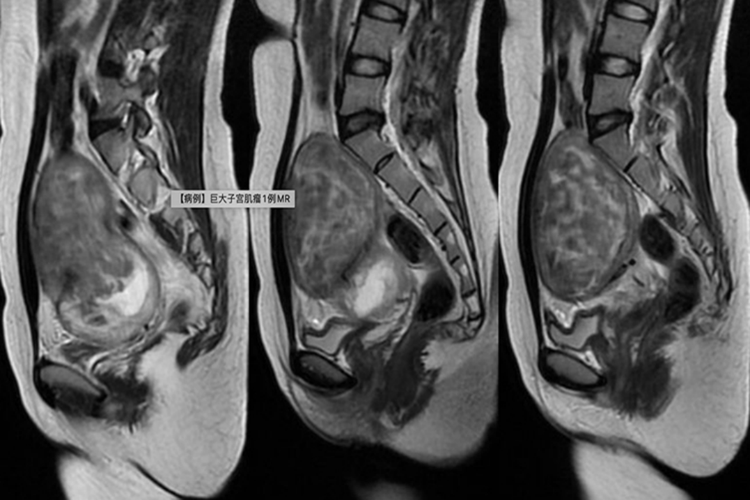

下腹包块:肌瘤较小时在腹部摸不到肿块,肌瘤较大时,患者自觉下腹部有肿块,为实质性,膀胱充盈时上升。当肌瘤逐渐增大使子宫超过3个月妊娠大时可从腹部触及,巨大的黏膜下肌瘤可脱出于阴道外,患者可因外阴脱出肿物就医。

对于子宫肌瘤需要结合肌瘤大小、部位、有无症状、年龄及生育要求等进行综合考虑。若肌瘤小且无症状,可随访观察。如为有症状的小肌瘤或已近绝经者,可考虑药物治疗。若上述治疗无效,或肌瘤大于三个月妊娠子宫,生长迅速及有恶变可能者,可考虑进行手术切除。